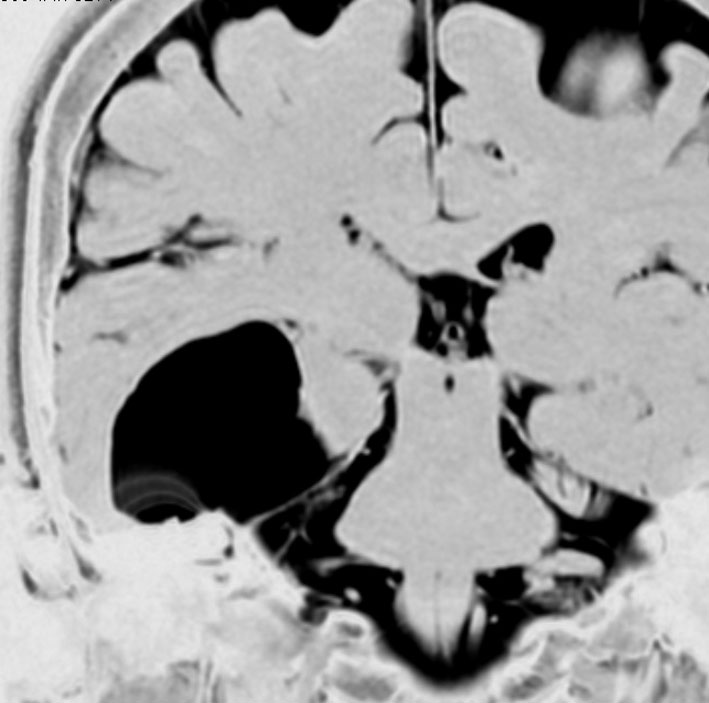

脳室内くも膜のう胞

くも膜のう胞が脳室内にできて,脳室の一部で髄液の流れをさまたげて,部分的な水頭症になることがあります。水頭症になっても停止性水頭症というもので悪化傾向がなければ治療の必要がありません。多くは側頭角というところが拡大するのですが,拡大傾向がはっきりしたら,内視鏡手術でくも膜のう胞の壁を切除します。

これは11歳の子供で偶然発見された右側脳室くも膜のう胞です。無症状で変化しませんからほっておきます。右のモンロー孔に狭窄があるために右側脳室だけの停止性水頭症になっています。